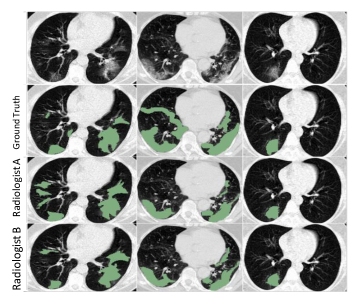

Figure 6: Pipeline of synthesizing COVID-19 positive CT volumes Ipssubscript𝐼𝑝𝑠I_{ps} and their pseudo labels Mpssubscript𝑀𝑝𝑠M_{ps}. Real healthy CT samples Ihsubscript𝐼I_{h} together with their lung segmentation masks Mlungsubscript𝑀𝑙𝑢𝑛𝑔M_{lung}, and COVID-19 CT samples Idsubscript𝐼𝑑I_{d} together with their predicted lesion segmentation masks M^^𝑀\hat{M} are needed. The green area of Mpssubscript𝑀𝑝𝑠M_{ps} represents the lesion (1), the yellow area is the part ignored when calculating loss (2), and the other areas represent the background (0). The last column in Fig. 7 follows the same rule.

Different from the synthesis method in [32], in which the distribution and shpae of lesions added to the healthy volumes are artificailly defined, the lesion area of our synthetic data is dynamically extracted from the real COVID-19 positive volumes. Different from [33], in which the synthetic volume is generated through complex cascade generative networks given a label map of lesion and lung, our synthetic data is formed by simple linear weighted fusion of real infectious areas and real health volumes. Fig. 7 gives three examples of Ipssubscript𝐼𝑝𝑠I_{ps} and corresponding Mpssubscript𝑀𝑝𝑠M_{ps}. The synthetic COVID-19 volumes look very natural and diverse. Relying on the generated paired data Ipssubscript𝐼𝑝𝑠I_{ps} and Mpssubscript𝑀𝑝𝑠M_{ps}, we can alleviate the problem of insufficient voxel-level labeled samples by adding corresponding voxel-level cross entropy loss ps=CSL(S(Ips;θs),Mps)subscript𝑝𝑠CSL𝑆subscript𝐼𝑝𝑠𝜃𝑠subscript𝑀𝑝𝑠\mathcal{L}_{ps}=\text{CSL}(S(I_{ps};\theta s),M_{ps}) to Ssubscript𝑆\mathcal{L}_{S} during the training. pssubscript𝑝𝑠\mathcal{L}_{ps} boosts the segmentation performance of GASNet by 5.5% in our experiments, as shown in section 5.

Refer to caption

Figure 7: Three examples of the generated COVID-19 positive CT volumes and their pseudo labels. From the first column to the fourth column are real COVID-19 CT volumes Idsubscript𝐼𝑑I_{d}, real healthy CT volumes Ihsubscript𝐼I_{h}, synthesized COVID-19 CT volumes Ipssubscript𝐼𝑝𝑠I_{ps}, and pseudo labels Mpssubscript𝑀𝑝𝑠M_{ps}.